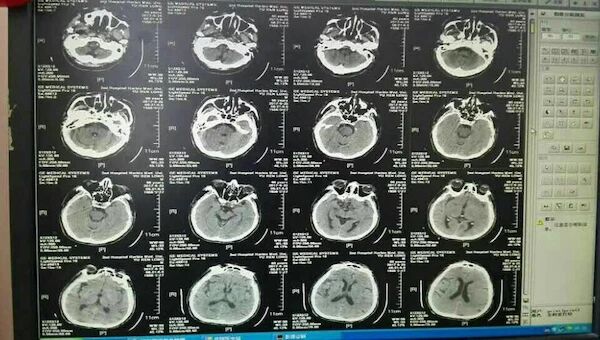

完善相关检查后,急诊行全脑血管造影术

示右侧大脑后动脉P1段不显影,右侧后交通动脉开放。左侧P1中段闭塞,左侧前循环无明显代偿。考虑该血管为责任血管,急诊行血管开通术。